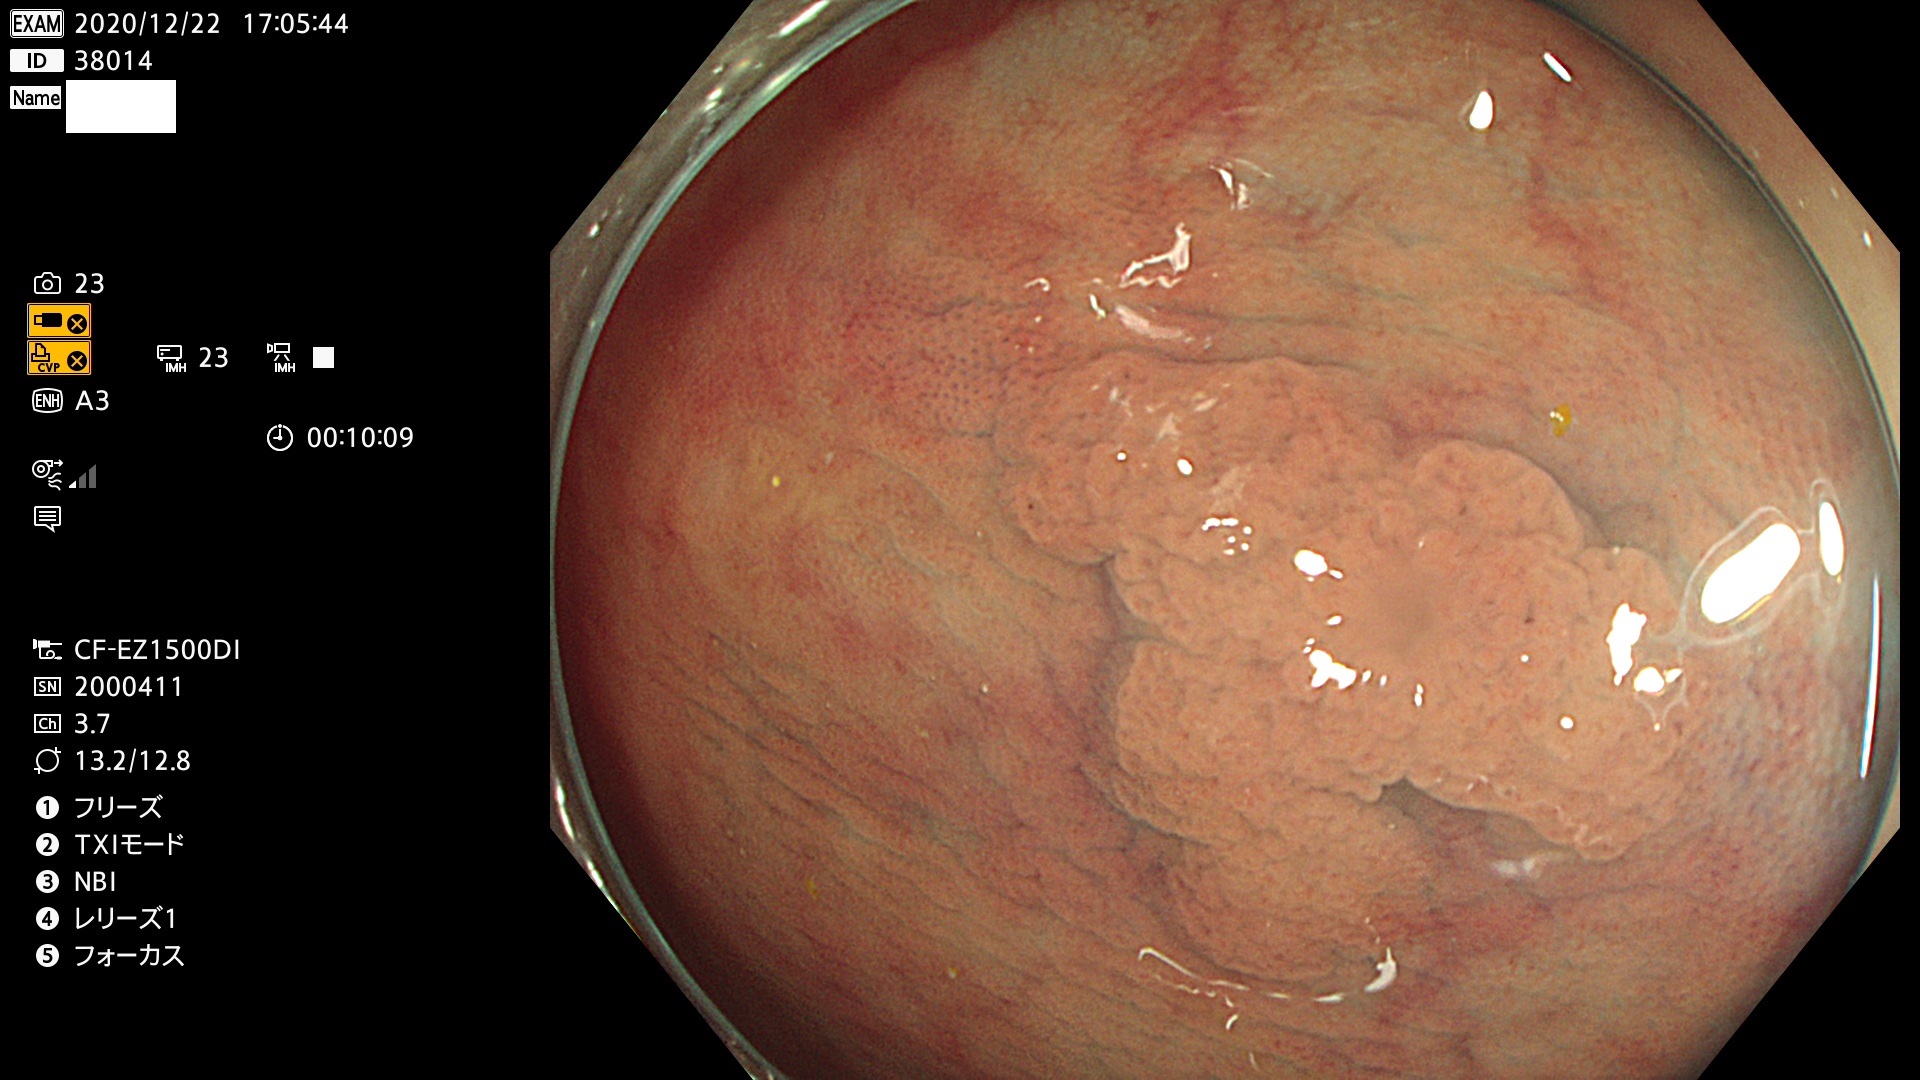

38001 38002 38003 38004 38006(SSAPのみ) 38007 38008 38009 38010 38012 38013 38014 38016 38018 38020 38021 38025 38026 38029 38032 38033 38034 38035 38036 38037(SSAPのみ) 38039 38043 38044 38048 38049 38050 38052 38055 38056 38057 38058 38059 38064(SSAPのみ) 38065 38068 38069 38070 38071 38072 38074 38075 38076 38078 38079 38080 38082 38083 38084 38085(SSAPのみ) 38086 38087 38088 38089 38090 38091 38092 38093 38094 38097 38098 38099

発見困難で危険性の高い平坦型病変(上記100名より抽出)